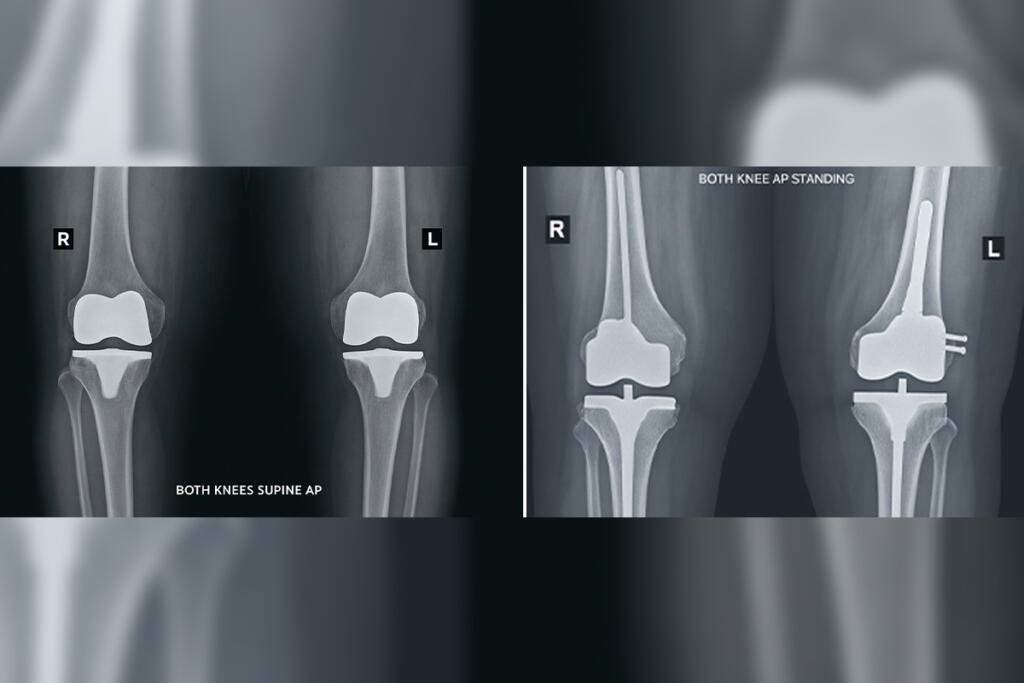

Primary Knee Replacement

Primary Knee Replacement is a surgical procedure that replaces a damaged knee joint with an artificial implant for improved function and pain relief...

Revision Knee Replacement

Revision Knee Replacement is a surgical procedure to replace a previously implanted artificial knee joint that has worn out or failed...